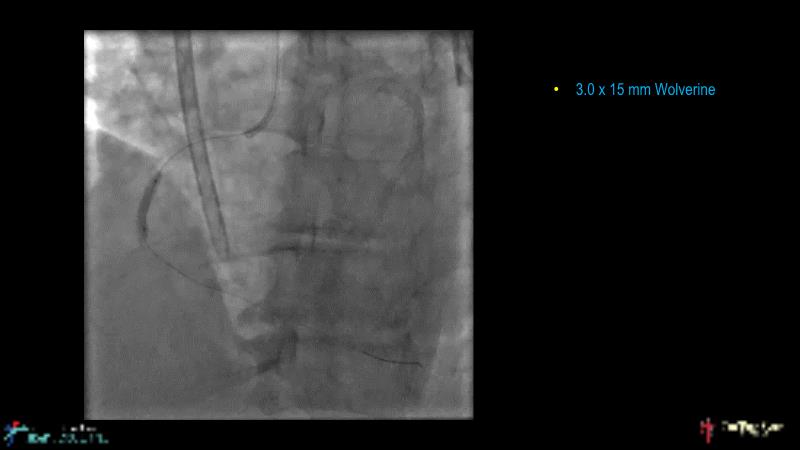

Cracking calcium: best practices to integrate intravascular lithotripsy into your calcium management algorithm

With this session, keep up to date on the evidence, trials and outcome data for intravascular lithotripsy in severely calcified lesions. Learn how to use this technique in real-world patients and understand its role in the treatment algorithm for severely calcified coronary lesions.